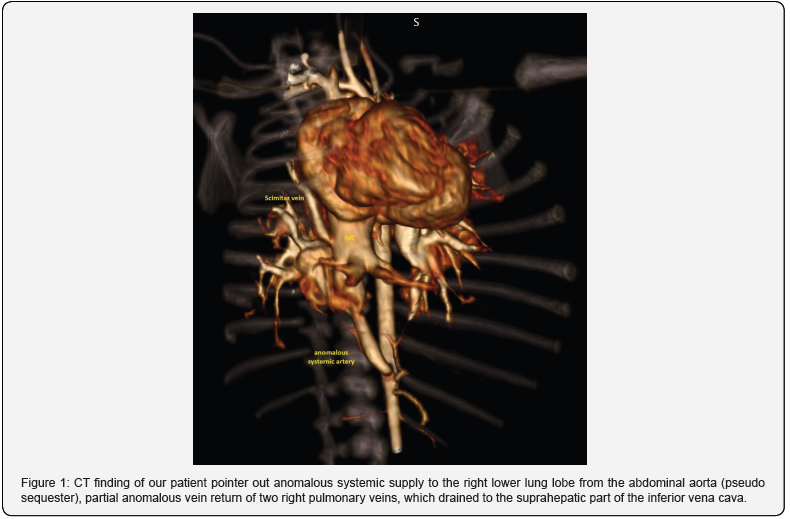

On admission, breath sounds were decreased on the right side, with bilateral rare inspiratory crackles and a systolic ejection murmur of II /VI in the third intercostal space. Two-dimensional echocardiography showed the right pulmonary artery maldevelopment and a moderate secundum-type atrial septal defect (ASD). Color Doppler examination revealed that the two anomalous pulmonary veins without stenosis entered the dilated inferior vena cava (IVC) just below the diaphragm with laminar flow. The blood vessel separated from the abdominal aorta and directed toward the right lung. Computed tomography (CT) showed anomalous systemic supply to the right lower lung lobe from the abdominal aorta (pseudo sequester), partial anomalous vein return of two right pulmonary veins, which drained to the suprahepatic part of the inferior vena cava, hypoplasia of the right lung with and right pulmonary artery (Figure 1). We diagnosed the infantile type of scimitar syndrome. Fiberoptic bronchoscopy pointed out bronchomalacia of the right bronchus. A controlled echocardiographic examination revealed severe pulmonary hypertension (moderate tricuspid regurgitation, pressure gradient of 75 mmHg; mild pulmonary regurgitation, pressure gradient of 37 mmHg); sildenafil was added.

On the 24th day of life, a body weight of 2.8 kg, cardiac catheterization, and angiography via femoral vein and artery with 4-French were performed under general endotracheal an aesthesia. An initial heparin bolus of 100 units/kg was administered. The mean pulmonary artery pressure was 51 mmHg, and the pulmonary to systemic blood flow (Qp/Qs) ratio was 2:1. The right pulmonary artery branch was significantly narrower than the left. Aortography showed the massive anomalous artery arising from the right anterior wall of the abdominal aorta above the celiac trunk, supplying blood to a localized region of the right lower lung (Figure 2). Its narrowest diameter was 4.3 mm; its largest transverse diameter was 6.8 mm, and its length was 19 mm. We selected a device 30% (7 mm) larger than the narrowest artery diameter [Amplatzer Vascular Plug 4]. The device was placed in the second curve via a 4F multipurpose catheter. Control angiography revealed slower flow and low contrast intensity through the deviated blood vessel and the absence of distal translocation of the device. After the procedure, according to the Institutional protocol, a continuous infusion of heparin was prescribed for 24 hours.